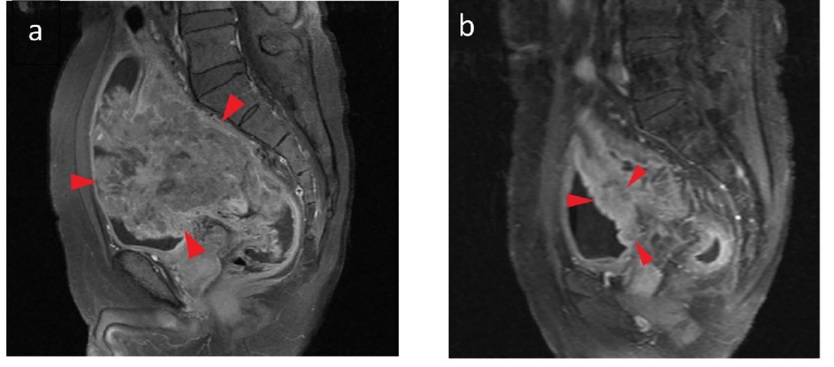

- CT, MRI: 직장암이 방광으로 침범했는지 여부 확인

출처 : ResearchGate